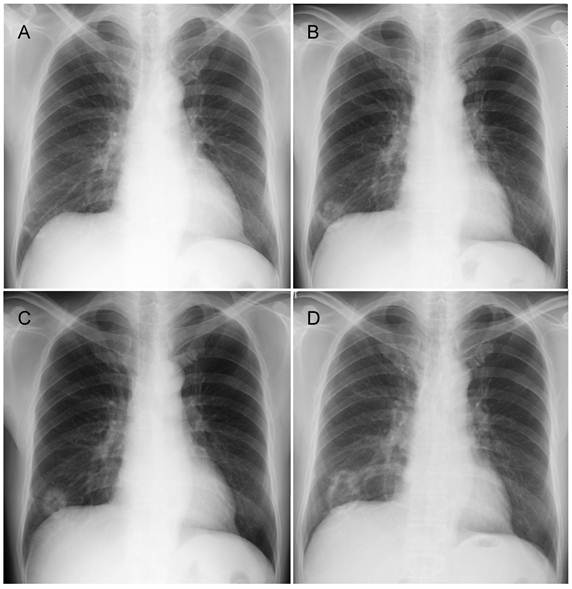

The patient was a 60-year-old man with a history of smoking 10 cigarettes per day for 35 years. He was found to have a small shadow in the right lower lung field on chest X-ray in 2006, and was thereafter followed-up at another hospital (Figure 1A). Chest X-ray in 2007 revealed a cavitating shadow at the same site (Figure 1B). A chest X-ray in 2008 showed thickening of the cavity wall, and that in 2009 revealed the tendency of the entire cavity shadow to enlarge (Figure 1C, D). He was referred to our department. Computed tomography showed an inhomogeneous thickening of the cavity wall and spiculation from the tumor margin, as well as the presence of lung structures in the cavity (Figure 2A). Bronchoscopic biopsy of the cavity wall led to a diagnosis of adenocarcinoma. Under a diagnosis of lung cancer (cT2aN0M0), right lower lobectomy with hilar and mediastinal lymph node dissection was performed.

Figure 1

Chest X-ray findings. A, B, C, and D show chest X-rays taken in 2006, 2007, 2008, and 2009, respectively. These X-rays revealed a lesion in the right lower lung field, which formed a cavity and enlarged over time.